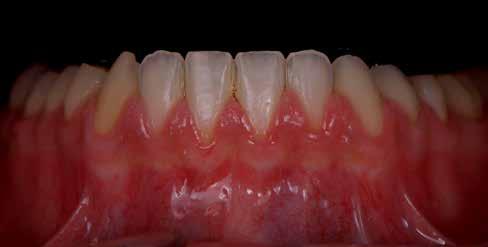

Amikor a 25 éves Andrea először konzultált a rendelővel, már több éve küszködött súlyos panaszokkal. Állapota két különböző betegségnek köszönhető, melyek egyrészt önmagukban, másrészt egymással kölcsönhatásban is súlyos következményekkel jártak. A fiatal nő veleszületett genetikai elváltozásban szenved, melynek tünete többek között a gyenge zománcfejlődés. Továbbá a beteget fibromyalgiával is diagnosztizálták, mely krónikus fájdalom rendellenesség, ami komoly tünetegyüttessel járó pszichés szorongás. A betegség egyik következménye az volt, hogy a páciens az elmúlt években átlagosan napi három-négyszer hányt. Az ebből fakadó savas erózió a már amúgy is veszélyben lévő fogazatot tovább roncsolta (2. ábra)

A betegség következményei

A páciens elviselhetetlen fájdalmakról számolt be, beleértve a többszörös szájüregi fertőzéseket is. Az elmúlt években az előírt számos antibiotikumos kezelés egyre gyengébb hatásfokkal működött. A fertőzések következtében több fogát is extrahálni kellett. A fogászati állapotával együtt az étkezés minősége is romlott. A súlyos esztétikai korlátok is terhet jelentettek. A psziché és az önbizalom komoly károkat szenvedett. Fogorvosnál tett korábbi látogatásai kellemetlen élményt jelentettek. Emiatt kezdetben vonakodott beleegyezni a komplex terápiába. Empatikus, érzékeny beszélgetések folyamán körvonalazódott számára a kezelés fontossága.

Pink, Pink V, 34V) (8. ábra). 2. ábra: A még meglévő fogak komoly károsodása. 3. ábra: A még meglévő fogak virtuális extrahálása. 4. ábra: Virtuális modellanalízis. 5. ábra: A harapási magasság megemelése 5,5 mm-rel és a fogforma kiválasztása a Digital Denture Full Arch könyvtár segítségével.